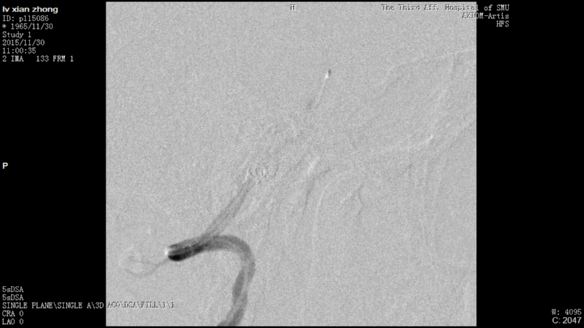

今天为大家分享的是“强生医疗CNV-神经介入专栏”第二十五期,由南方医科大学第三附属医院神经外科主任黄理金教授带来的“Enterprise支架辅助栓塞动脉瘤的优势”精彩讲课视频及PPT,欢迎观看。文章仅代表作者个人观点,如有不同见解,欢迎同道斧正!